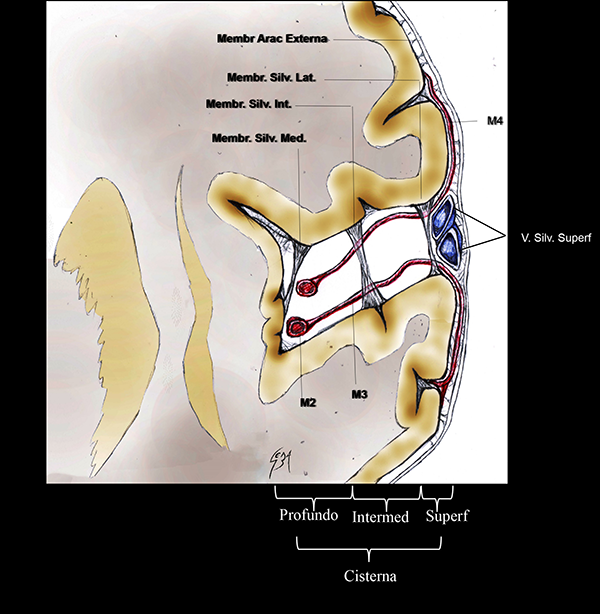

Figura 2: Dibujo esquemático de una vista coronal de la FS izquierda con sus membranas aracnoideas. La cisterna silviana se sitúa entre la membrana aracnoidea externa y la piamadre. Su parte lateral tiene 3 membranas silvianas internas que dividen el espacio subaracnoideo: lateral, intermedia y medial. Membr Arac: membrana aracnoidea; Membr Silv: membrana silviana. V. Silv. Superf: venas silvianas superficiales. Intermed: intermedio.

En un completo estudio de Inoue et al.,28 se describe a la cisterna silviana limitada por la membrana aracnoidea externa y la piamadre. Numerosas trabéculas y membranas internas cruzan a lo largo de ella, dividiendo al espacio subaracnoideo en compartimientos más pequeños (Figura 2).

Las membranas aracnoideas intrasilvianas de la cara lateral de la FS son esquematizadas en 3, acorde a la literatura:28 la membrana lateral, intermedia y medial. La membrana silviana lateral es la más superficial. El trayecto de las venas silvianas superficiales y el segmento M4 de la ACM se ubica entre esta membrana y la membrana aracnoidea externa. Se adhiere a los márgenes laterales de los opérculos frontoparietotemporales. La membrana silviana intermedia se relaciona con la porción medial de los opérculos y se localiza lateral al segmento M2. La membrana silviana medial es la más profunda de todas y se localiza medial a M2. Está adherida al margen más profundo del opérculo frontoparietal y la corteza insular (Figura 2).28

La membrana aracnoidea silviana intermedia divide arbitrariamente al aspecto lateral de la cisterna silviana en dos compartimientos.28 Medial a esta membrana, se ubica la hendidura insular lateral. Las venas silvianas profundas y el segmento M2 se localizan en este compartimiento. Lateral a la membrana silviana intermedia, se encuentra el compartimiento opercular lateral (Figura 2).